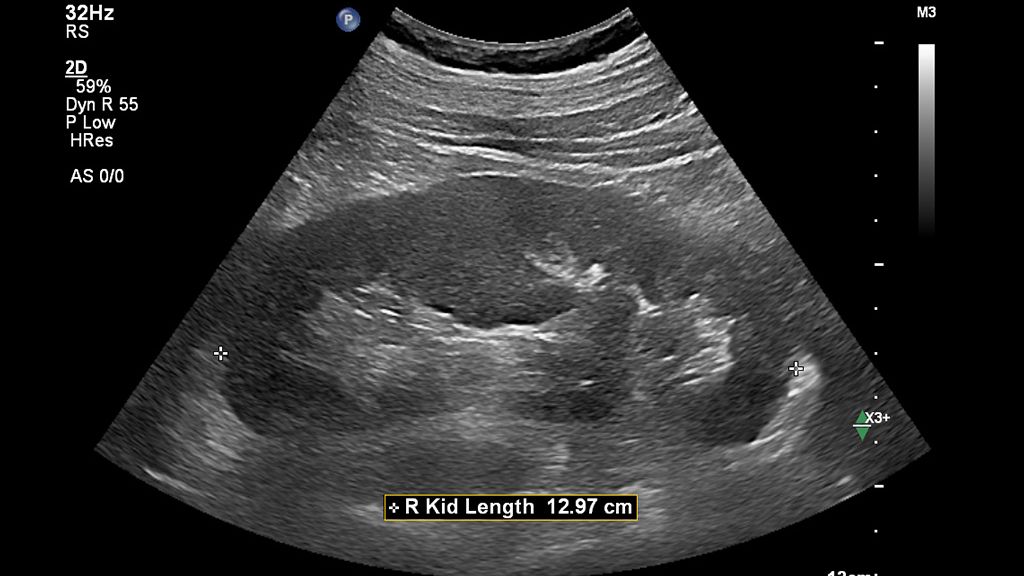

AI-driven Auto Measure Abdomen - Philips